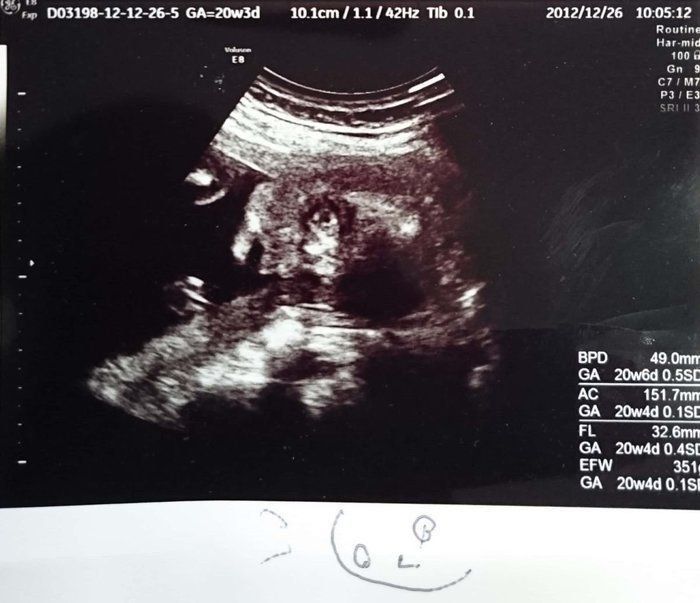

つぼいみきさんの妊娠20週目のエコー写真 胎動を感じ始める

推定体重400g 胎動を感じ始める

左写真には足2本が確認できます。この状態を見て先生に「確実に女の子でしょうね」と言われました。右は顔がうつっています。前回の検診の時よりさらにお顔がはっきりし、「輪郭はシャープだからパパ似かな?」と夫婦の会話も弾んでいました。胎動もポコッポコッと感じるようになり、パパも手をあてて胎動を感じることができ喜んでいました。前回の検診で私の体重が増えないことに悩んでいたはずが…この日の検診では1ヶ月で2.8kgも体重が増加。「一気に増えるのは良くないから少し気をつけようね」と先生から指摘を受けました。